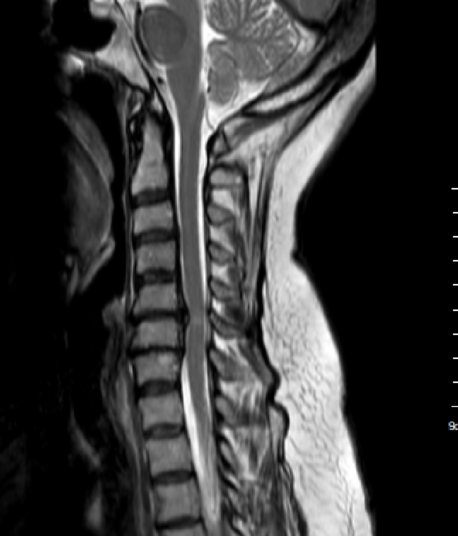

Resonancias magnéticas y radiografías

La resonancia magnética (RM) es uno de los estudios más efectivos, ya que proporciona imágenes detalladas de los tejidos blandos, incluyendo la médula espinal y los discos intervertebrales. Las radiografías son útiles para evaluar la alineación de las vértebras y detectar cambios óseos.